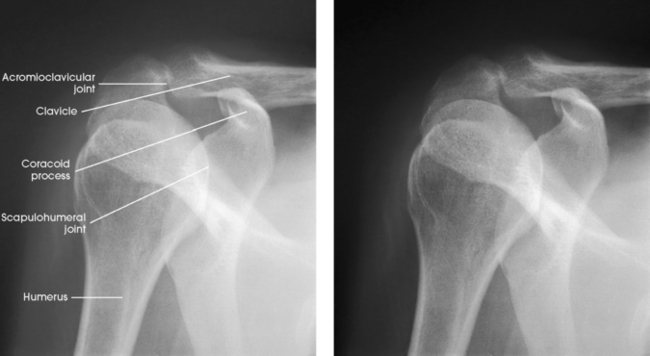

Structures shown: The joint space between the humeral head and the glenoid cavity (scapulohumeral joint) is shown (Figs. 5-19 and 5-20).

Structures shown: The scapulohumeral joint (Fig. 5-22) is seen.

Fig. 5-22 A, AP oblique projection: Grashey method, with shoulder showing normal scapulohumeral joint space. B, AP oblique projection: Apple method, with weighted abduction showing loss of articular cartilage (arrow).